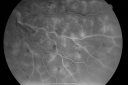

49-year-old woman has central retinal vein occlusion right eye with fluctuating vision and then recently her vision declined and she developed macular edema. I was worried about her angle and you were kind enough to do a peripheral iridotomy and I am dilating her today. Her vision is still poor. VISUAL ACUITY: OD 20/100. IOP: OD 20. There is a peripheral iridotomy, lens is clear, there is no rubeosis. EXTENDED OPHTHALMOSCOPY: OD: Vertical C/D ratio is 0.1. There is 2+ optic nerve edema, 3+ cystoid macular edema. The retinal veins are dilated in all 4 quadrants. The photos confirm clinical findings. Fluorescein angiogram shows some substantial delay in the venous circulation time with no non-profusion. IMPRESSION: 1. PERFUSED CENTRAL RETINAL VEIN OCCLUSION RIGHT EYE. 2. MACULAR EDEMA IN THE RIGHT EYE. DISCUSSION: I explained to the patient that with intravitreal Kenalog there is about an 80% chance of drying up the macula and improving the vision. There is a risk of cataract and glaucoma and a very low risk of infection. I injected the eye today without difficulty with the Kenalog.